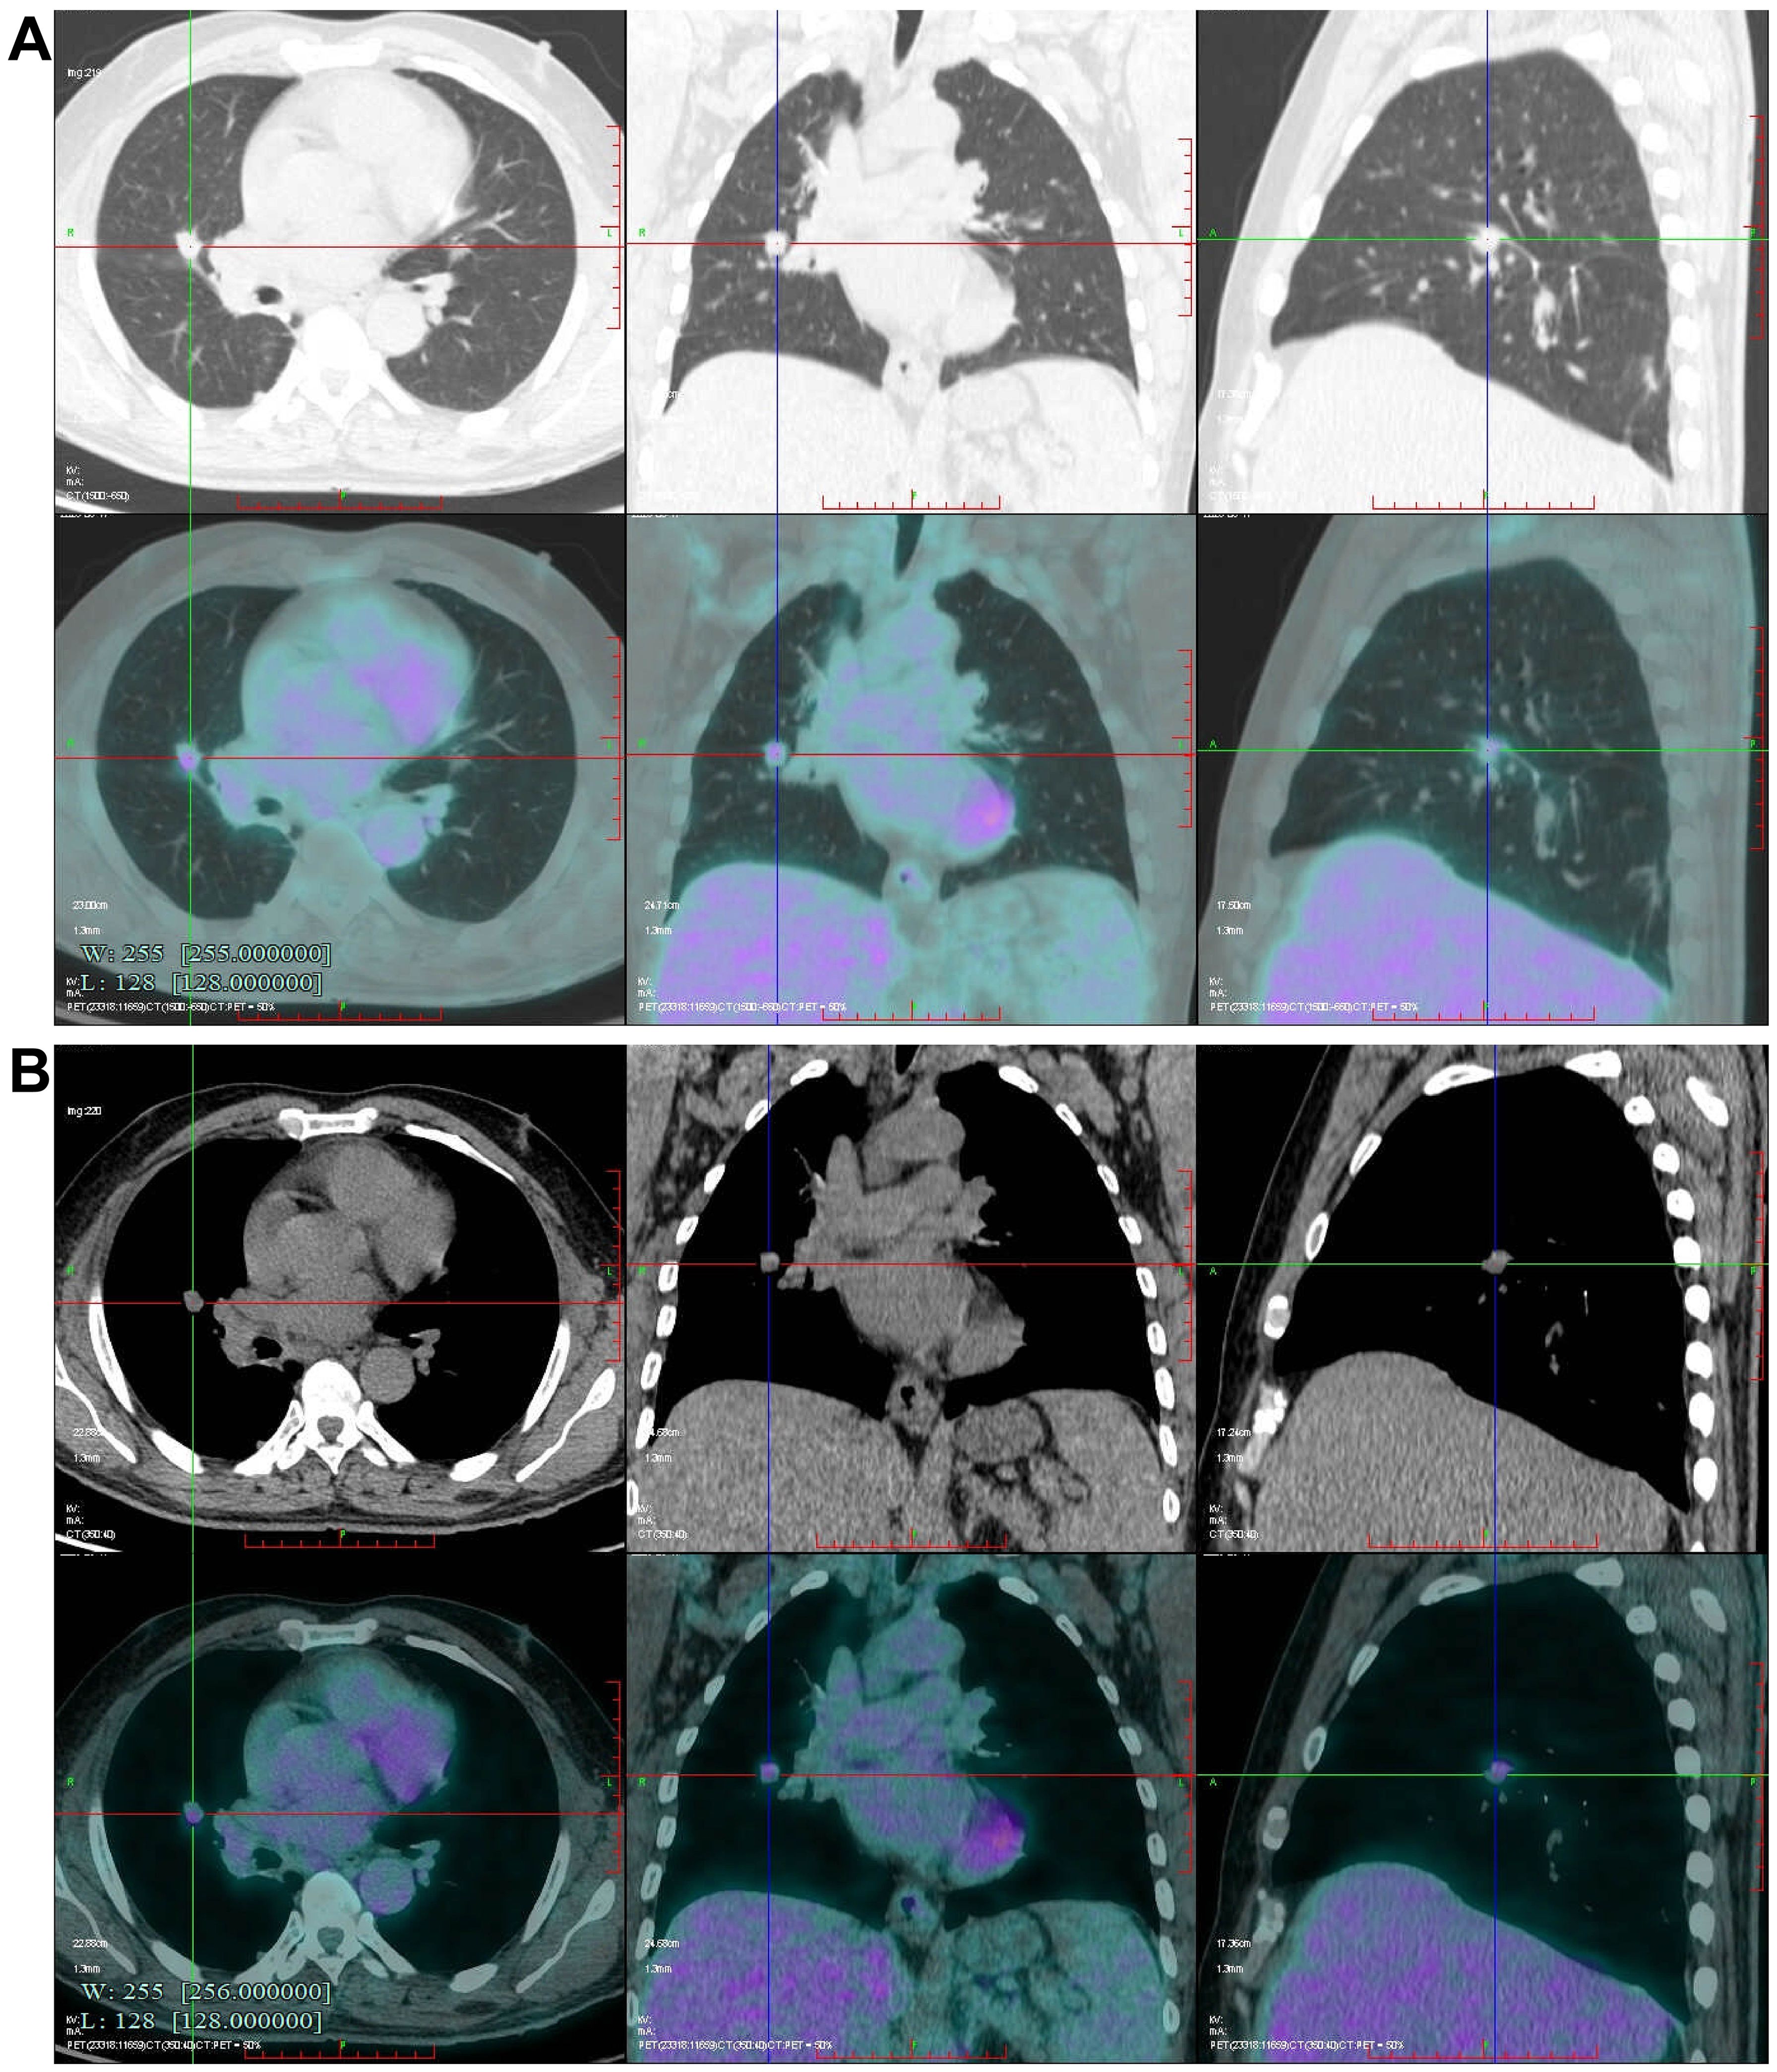

Abstract: This article presents a case study of a patient with early-stage lung cancer who received comprehensive management at our institution throughout the entire clinical course. During follow-up, multiple progressively enlarging solid nodules were detected in the right lung and pleural cavity. Positron emission tomography-computed tomography (PET-CT) demonstrated increased fluorodeoxyglucose (FDG) uptake in these nodules, with a maximum standardized uptake value (SUVmax) of 3.568. Following a multidisciplinary team (MDT) discussion, surgical resection of the nodules was undertaken. Pathological examination confirmed the diagnosis of necrotizing sarcoid granulomatosis (NSG), with special staining and microbiological testing yielding negative results, thereby excluding infectious lesions and tumor metastasis. This case highlights the critical importance of distinguishing metastatic tumors from NSG when new intrapulmonary or pleural nodules appear post-lung cancer surgery. Surgical biopsy is demonstrated to be an effective modality for achieving a definitive diagnosis.